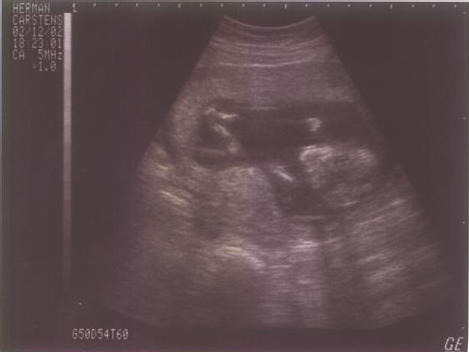

13

Semanas |